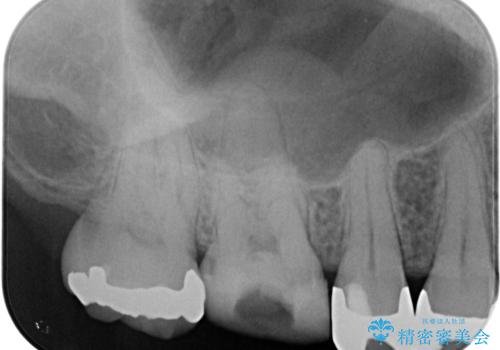

- 近医にて治療を行っていたものの、痛みがなかなか引かないとのことで転院されてきた患者様です。

上下で接触しないように削られていたため、日常生活で痛みを感じることはありませんでしたが、歯を叩くと痛みを感じる状態でした。

前医ではラバーダムの装着をされていない状態で根管治療を行っていたようで、その他の器具や処置も無菌的環境下であったとは考えにくいため、それが痛みがなかなか引かない原因の一つであると考えられました。

根管治療後に痛みの消失を確認し、オールセラミッククラウンにて補綴治療を行うこととしました。